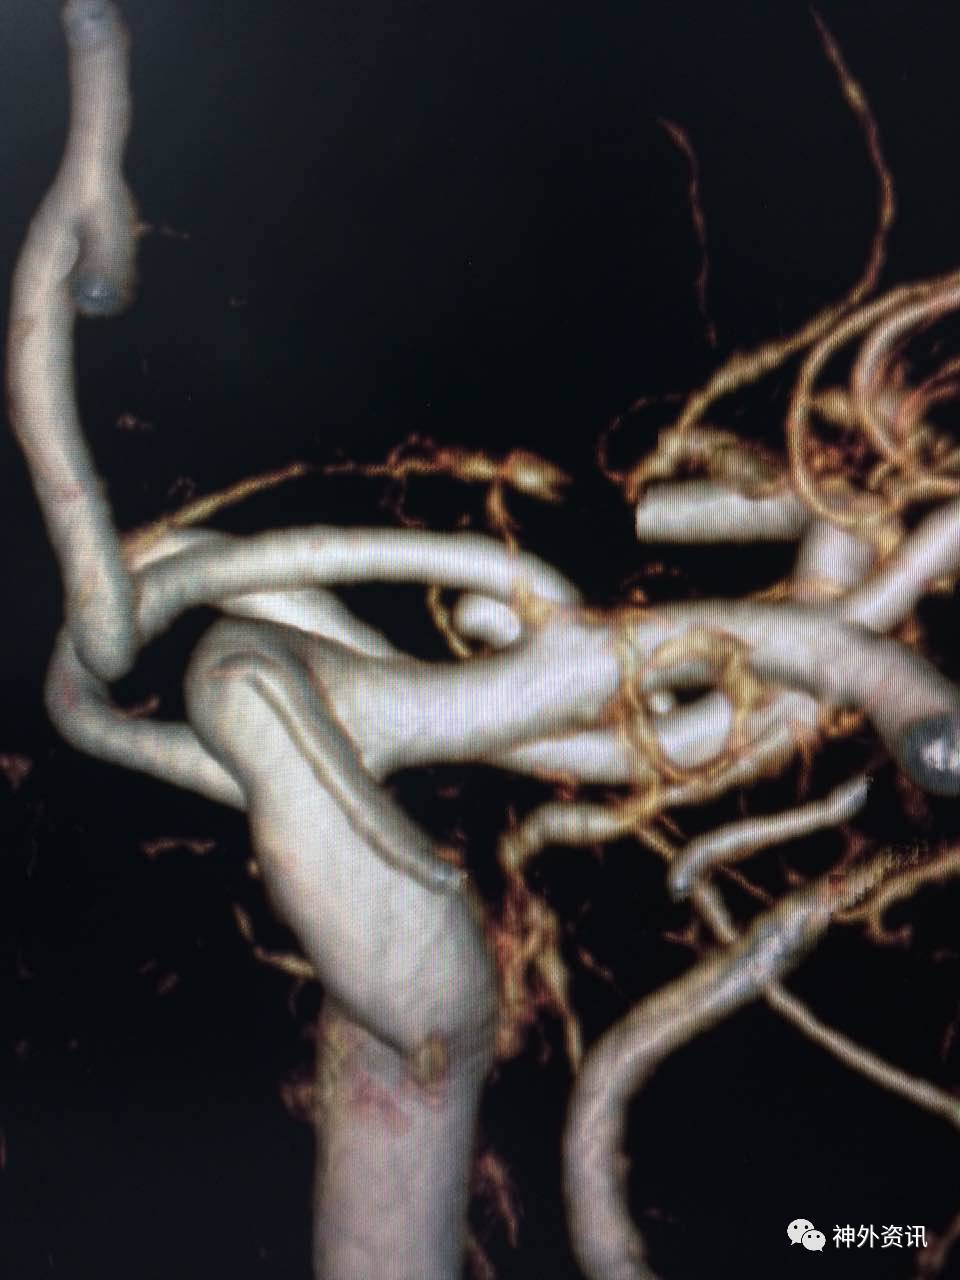

复合立体塑形

塑形考虑血管走行,但是血管内径过大(约>3mm,例如颈内动脉)的情况下,微导管在血管内是螺旋前进(2维是折线前进),即使顺行也需要考虑改变角度。

非同一平面内的弯曲: